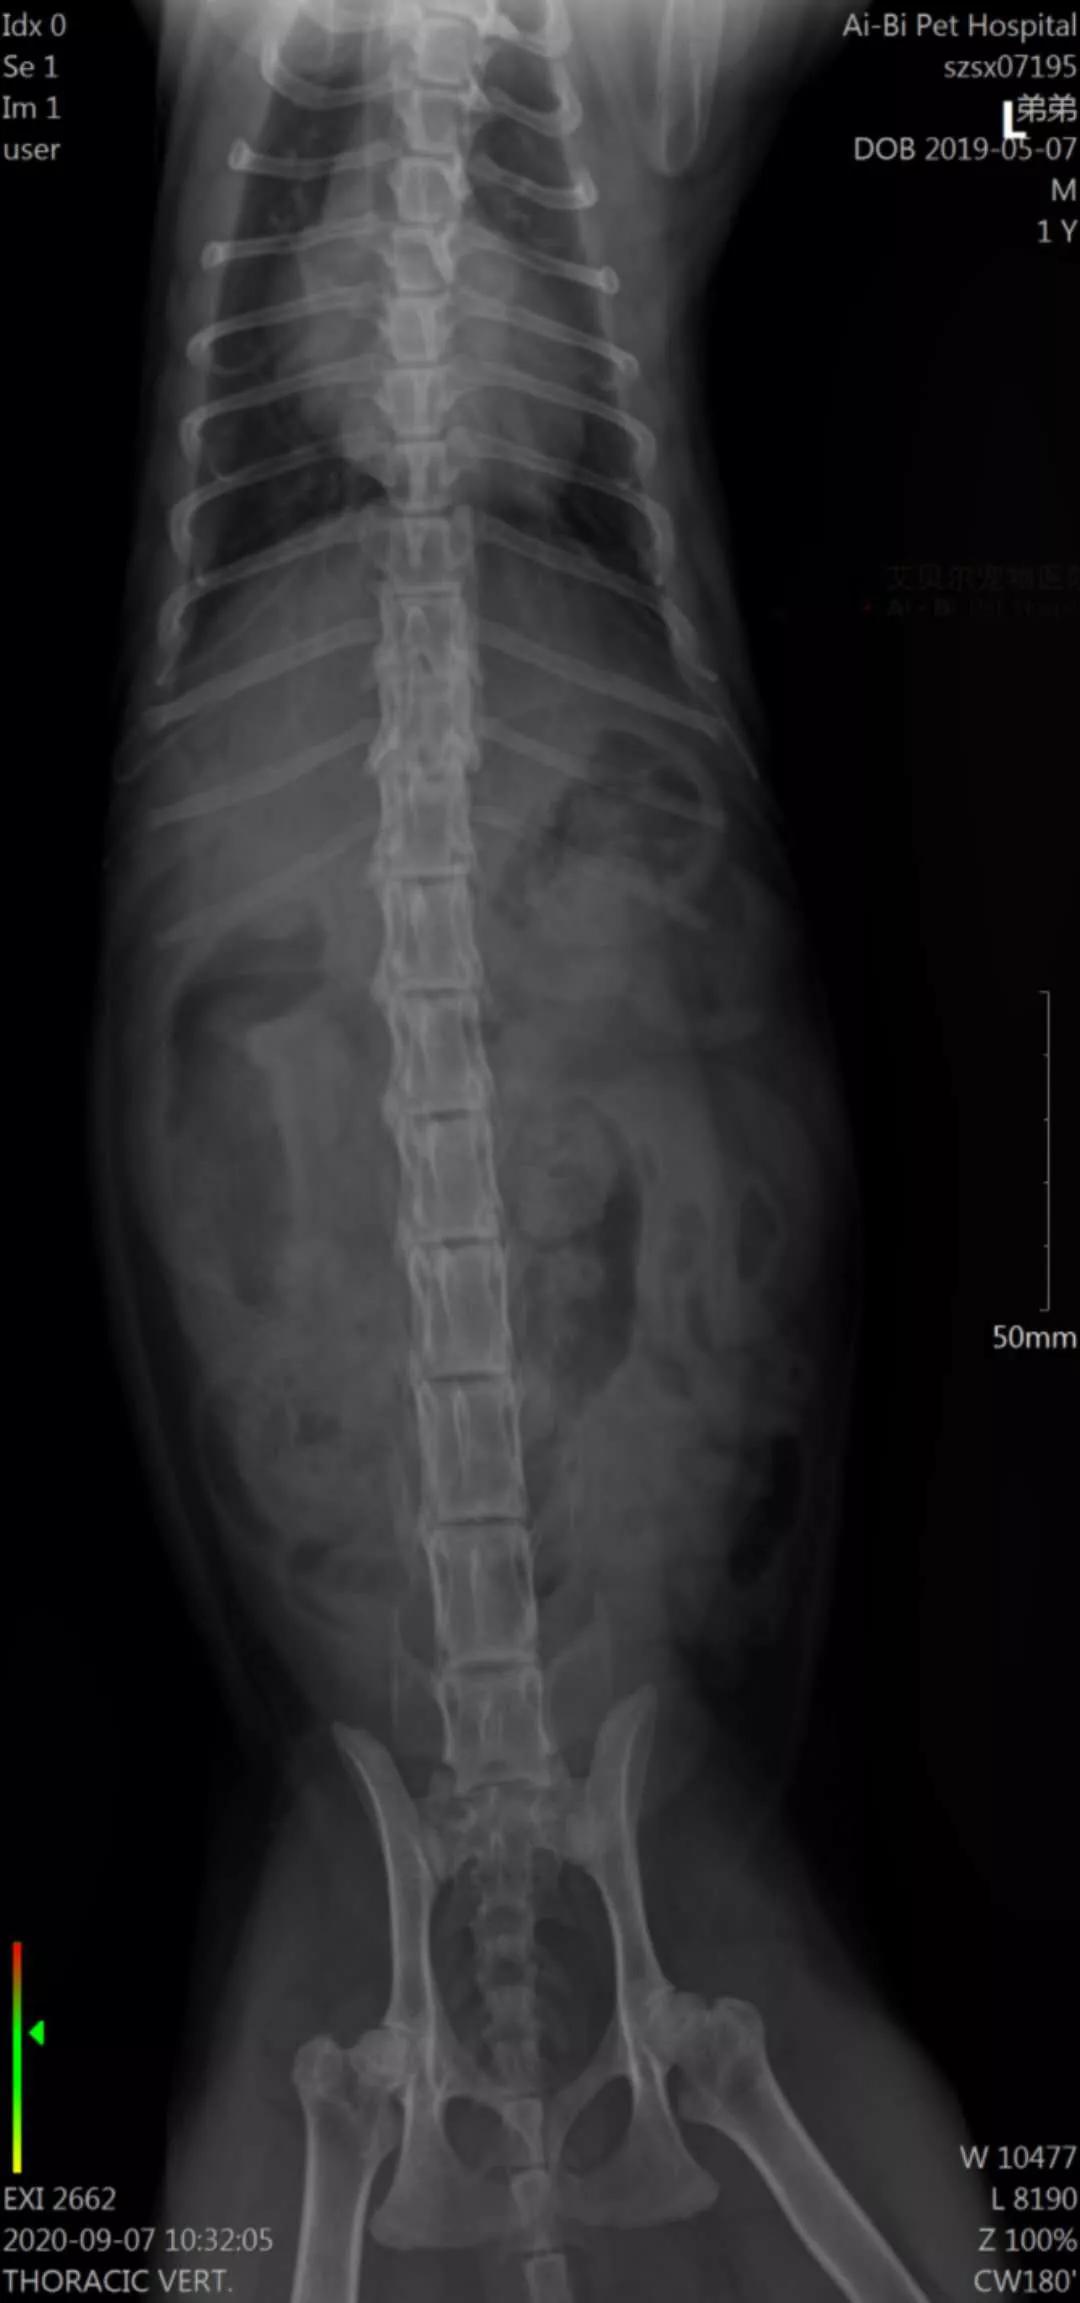

弟弟的病情十分突然,短短三天便无法走路,让人猝不及防。弟弟的主人心急如焚,在网上了解到曹浪峰宠物医院的针灸疗法,立即将弟弟转诊过来。经过X光片诊断,弟弟的腰椎先天性错位,导致双后腿急性瘫痪。